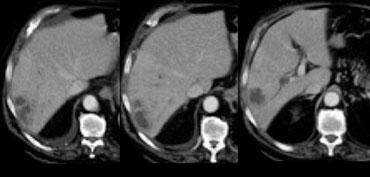

Ung thư biểu mô tế bào gan kích thước nhỏ trên nền gan xơ: không quan sát thấy trên CT không tiêm thuốc (trái), hiện rõ trong thì động mạch (giữa) và không quan sát thấy trong thì tĩnh mạch cửa (phải)

Khả năng phát hiện một tổn thương gan phụ thuộc vào sự chênh lệch tỷ trọng giữa tổn thương và nhu mô gan bình thường.

Trên CT không tiêm thuốc cản quang (NECT), các khối u gan thường không quan sát được do độ tương phản vốn có giữa mô u và nhu mô gan xung quanh quá thấp.

Do đó, cần tiêm thuốc cản quang tĩnh mạch để tăng khả năng hiển thị của các tổn thương.

Khi tiêm thuốc cản quang tĩnh mạch, cần hiểu rằng gan có nguồn cung cấp máu kép.

Nhu mô gan bình thường được cung cấp máu 80% từ tĩnh mạch cửa và chỉ 20% từ động mạch gan, do đó sẽ ngấm thuốc trong thì tĩnh mạch cửa.

Tuy nhiên, tất cả các khối u gan đều nhận 100% nguồn cung cấp máu từ động mạch gan, vì vậy khi ngấm thuốc sẽ xảy ra trong thì động mạch.

Sự khác biệt về nguồn cung cấp máu này dẫn đến các kiểu ngấm thuốc khác nhau giữa khối u gan và nhu mô gan bình thường trong các thì tiêm thuốc cản quang khác nhau (hình).